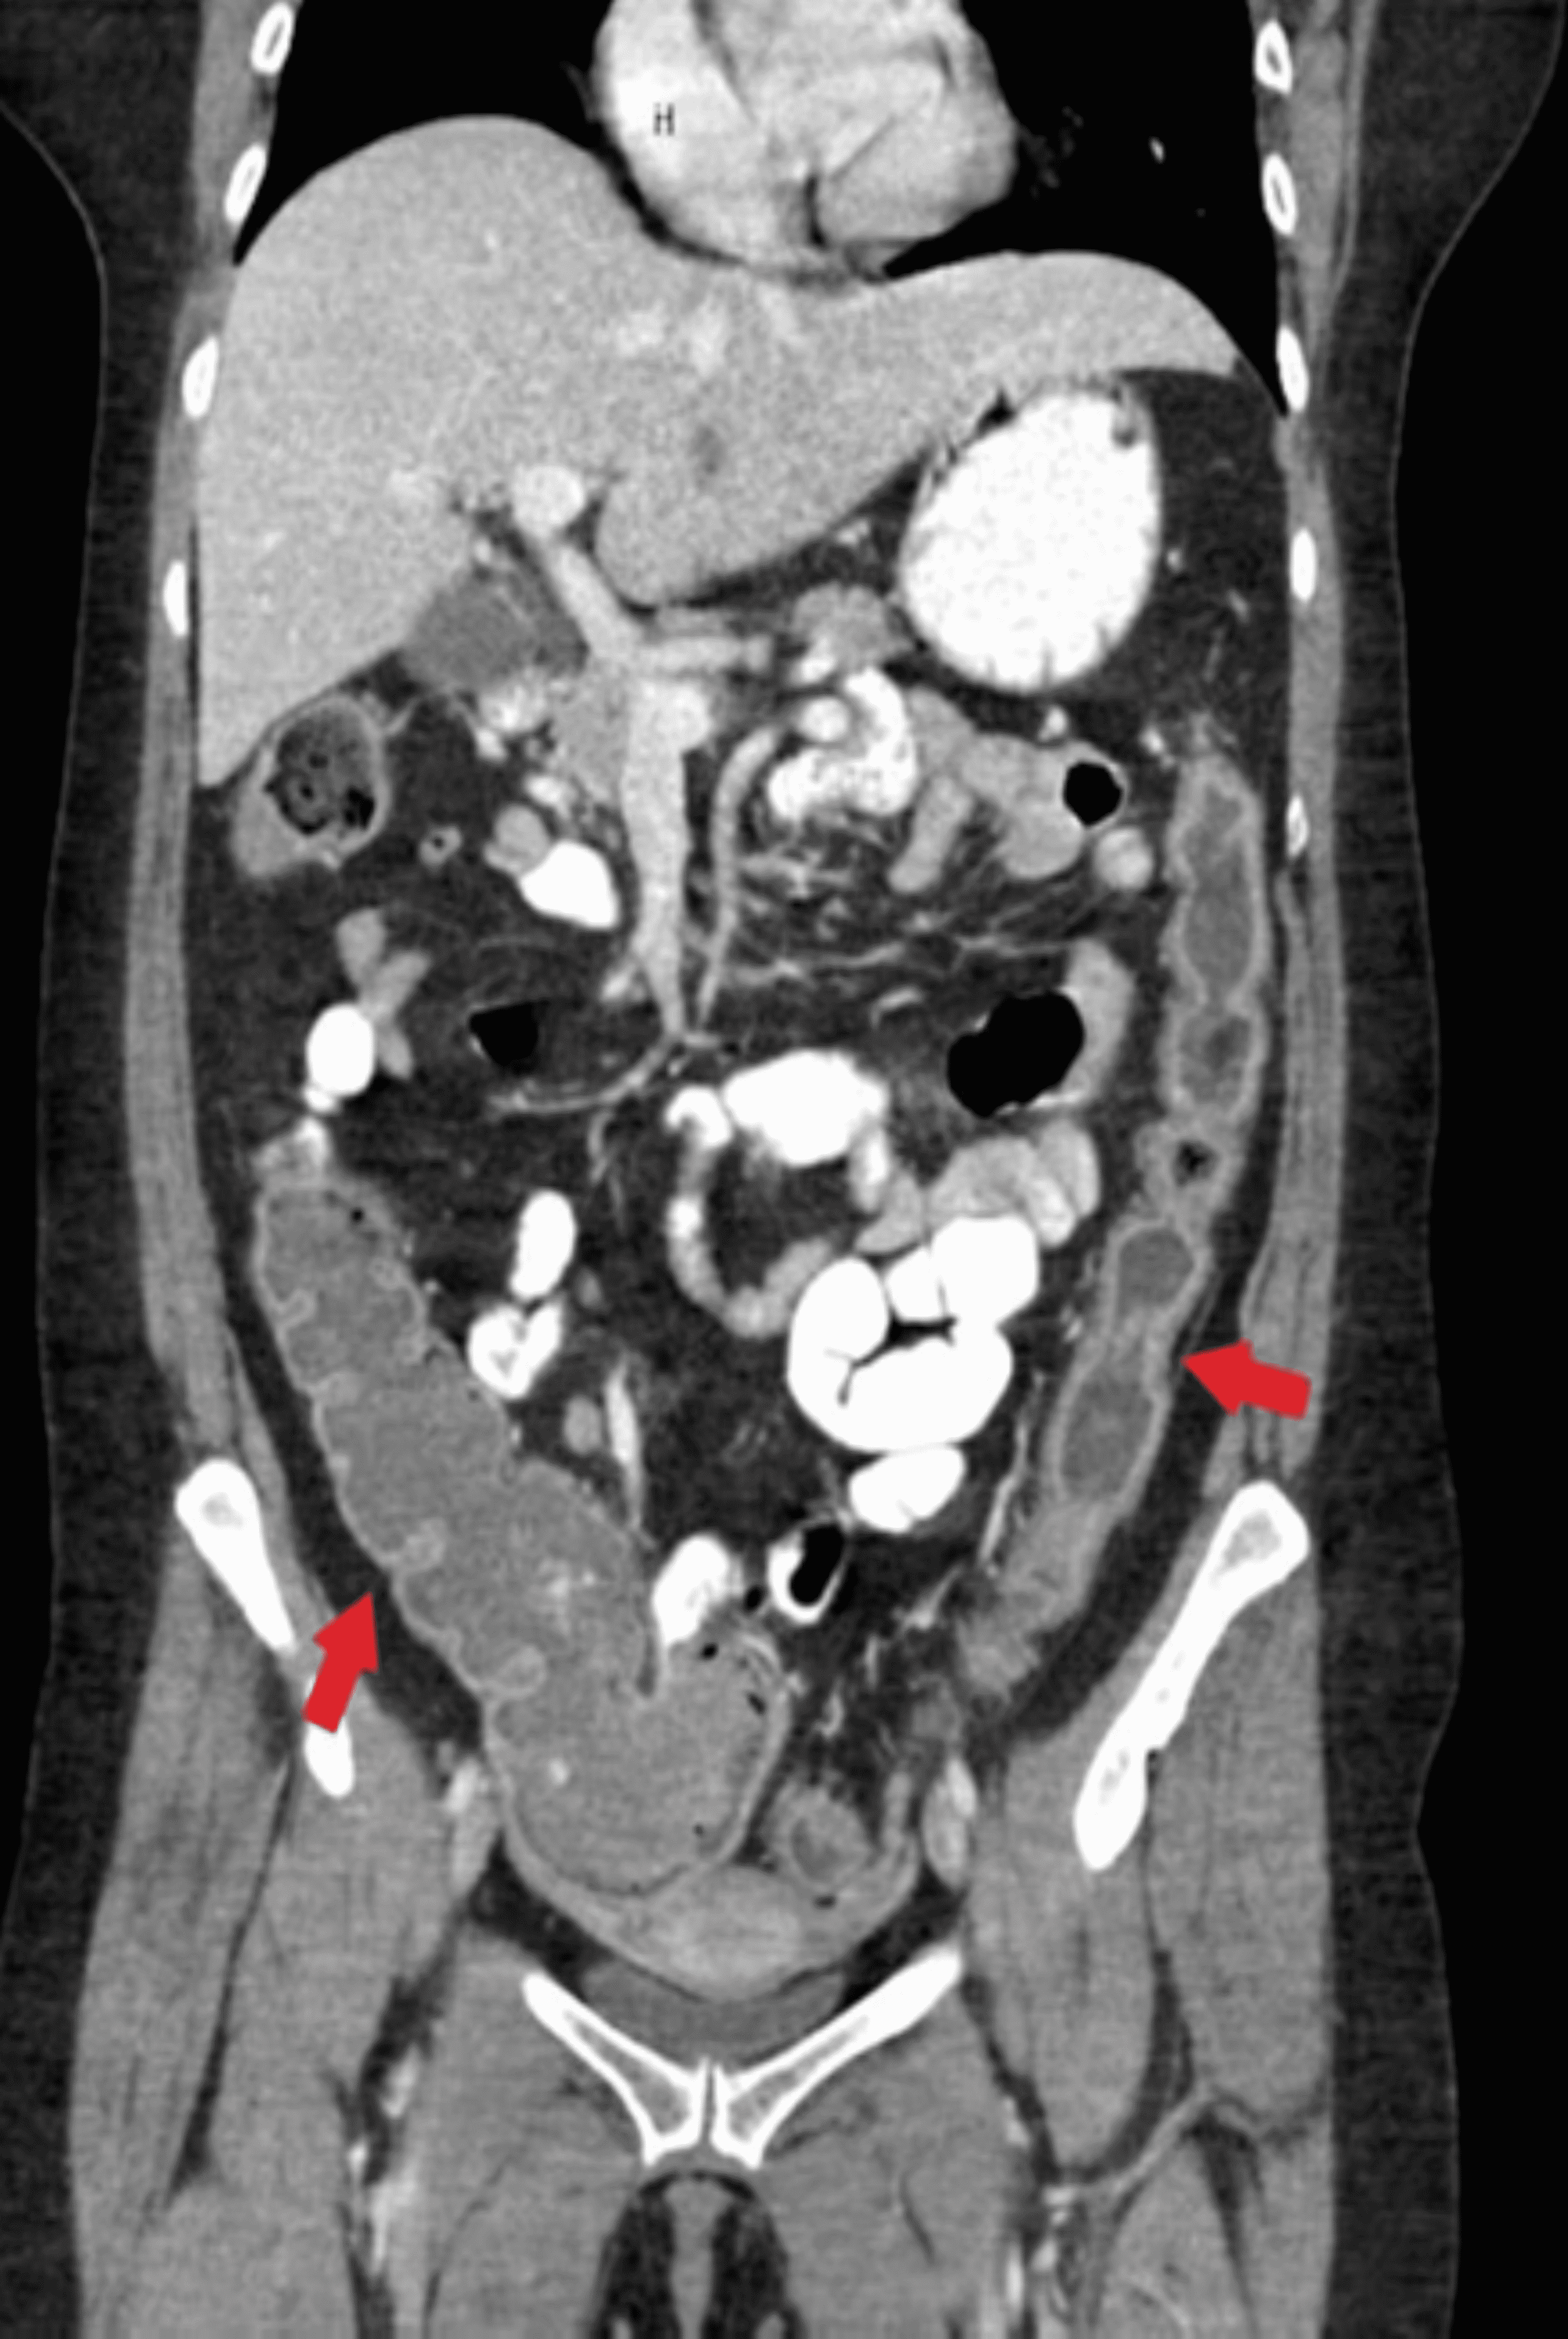

From www.cureus.com

Cureus Refractory Fulminant Colitis Requiring Surgical Intervention Red Light Therapy Ulcerative Colitis researchers are exploring the use of uv light to alter the gut microbiome and treat mild ulcerative colitis. phase ii results suggest targeted therapy is effective for moderate to severe ulcerative colitis. Ulcerative colitis (uc) is an inflammatory disease of the large intestine. ulcerative colitis (uc) is a chronic and progressive inflammatory disorder that affects the colon. Red Light Therapy Ulcerative Colitis.